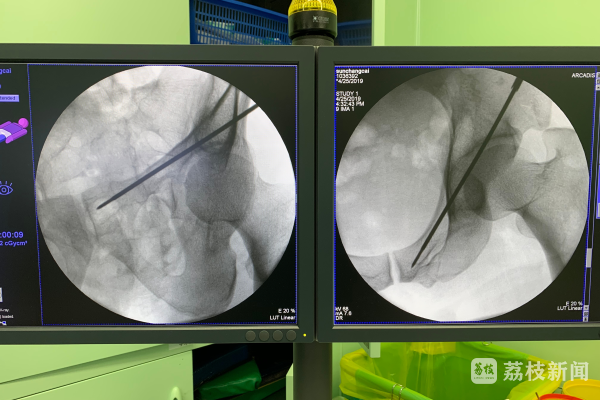

今年86岁的王大爷,平常喜欢坐公交车到处走走,活动筋骨。不久前的一天,王大爷和往常一样上了公交车。可让王大爷没想到的是,公交车在通过路面减速带的时候,车子颠了一下。就是这轻轻的一颠,王大爷就感到身体“咯噔”一声,紧接着腰部传来疼痛感。王大爷当时就不能活动了。司机赶紧把王大爷送到医院,检查结果显示王大爷腰部椎体压缩性骨折,原因是王大爷有严重的骨质疏松症。好在王大爷是幸运的,经过及时治疗,王大爷已经顺利出院。

经医生的初步诊断,赵大爷髋部骨折,李奶奶腰椎骨折,原因也是因为两人有严重的骨质疏松。最可怕的是,因为年龄比较大,赵大爷有严重的基础疾病,手术风险巨大。最终,赵大爷因为合并并发症,永远的离开了李奶奶。李奶奶出院后,行动能力也受到很大影响。

人的大腿根部就是医学上说的髋部。临床上有一种说法,把老年人的髋部骨折称为“人生最后一次骨折”。根据世界卫生组织统计,老年髋部骨折如果不做任何处理,一年内的死亡率在20%-50%。江苏省人民医院骨科主任医师、应急办主任陈群说:“这就是‘人生最后一次骨折’名称的由来。”

骨质疏松最可怕的并发症就是骨折。许多骨质疏松患者就诊时反映,自己就是弯腰系鞋带或者打个喷嚏,就发生了骨折。骨质疏松症最常见的骨折部位为脊柱椎体、髋部和腕部。这些部位发生骨折对患者的生活质量有很大影响,而且很容易出现下肢深静脉血栓、坠积性肺炎和褥疮等并发症,甚至危及生命。